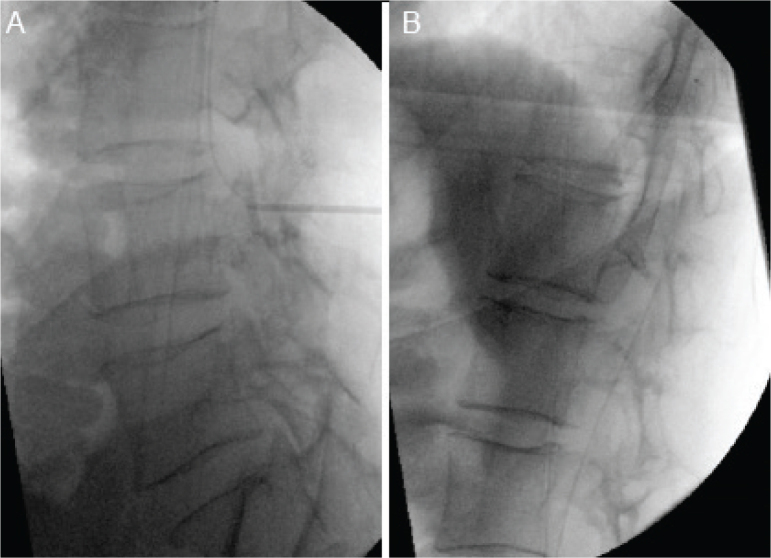

本病例是一名 35 岁男性患者,患有脊柱占位性神经纤维瘤病-1(spinal predominant neurofibromatosis-1),出现了不完全脊髓损伤(C3 Asia C),尽管对多发性颈椎神经纤维瘤进行了紧急减压手术,但病情仍不见好转。本报告概述了鞘内注射巴氯芬的新适应症。患者下肢无力并伴有严重痉挛,所有活动至少需要两人协助。康复治疗的目的是改善患者的整体肌张力,同时注重患者的独立性、活动能力和生活质量。在成功试用了鞘内巴氯芬后,他接受了鞘内巴氯芬泵植入手术。在他接受渐进式伸展和功能康复治疗的同时,剂量也在逐渐增加。6 周后,他的 MAS 已提高到 1-2/4,并已能独立转移、独立进行大多数日常生活活动,而且只需极少的支持就能出院回家。

This case presents a 35-year-old male with spinal predominant neurofibromatosis-1 who developed an incomplete spinal cord injury (C3 Asia C) which did not improve despite urgent decompressive surgery for multiple cervical neurofibromas. This report outlines a novel indication for intrathecal baclofen. The patient suffered from lower limb weakness with severe spasticity and required assistance of at least two for all activities. The aim of rehabilitation was to improve overall tone while focusing on independence, mobility and quality of life. After a successful trial of intrathecal baclofen, he underwent implantation of an intrathecal baclofen pump. The dose was gradually increased while he received a progressive programme of stretching and functional rehabilitation therapy. After 6 weeks, his MAS had improved to 1-2/4 and he had progressed to independent transfers, independence for most activities of daily living and was able to discharge to his family home with minimal support.